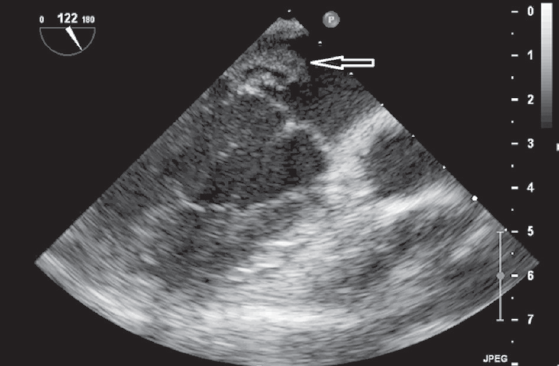

Оптимальные сроки операции на клапанах сердца у пациентов с активным инфекционным эндокардитом (ИЭ) до сих пор остаются спорными. Общеизвестно, что наиболее частой причиной смерти больных с левосторонним ИЭ является системная тромбоэмболия, поражающая церебральные, коронарные или почечные сосуды, которая может развиться еще до появления клинических проявлений поражения клапанного аппарата сердца. В настоящее время раннее хирургическое вмешательство рассматривается как наиболее эффективный метод лечения большинства форм активного ИЭ с поражением левых отделов сердца, которое подразумевает под собой выполнение хирургической коррекции еще до завершения полного терапевтического курса антибиотиков. Представляется клинический случай раннего успешного хирургического лечения инфекционного эндокардита митрального клапана (МК) у пациентки А., 16 лет. Заболевание протекало остро, с рецидивирующими эмболиями, повлекшими за собой инфаркт правой почки, а также остеомиелит левой ключицы. Хирургическое вмешательство производилось в срочном порядке из правосторонней переднебоковой торакотомии. Операция была проведена на 4-е сутки от момента госпитализации в кардиохирургический стационар. Однако потеря времени на догоспитальном этапе лечения, стремительное развитие грубых деструктивных изменений на МК, к сожалению, не позволили выполнить реконструктивное вмешательство. Произведено протезирование МК. Течение послеоперационного периода гладкое, на 3 сутки девочка была переведена в общесоматическое отделение. При контрольной эхокардиографии через 3 года сократительная функция миокарда сохранена, фракция выброса 65 %, функция протеза не нарушена.